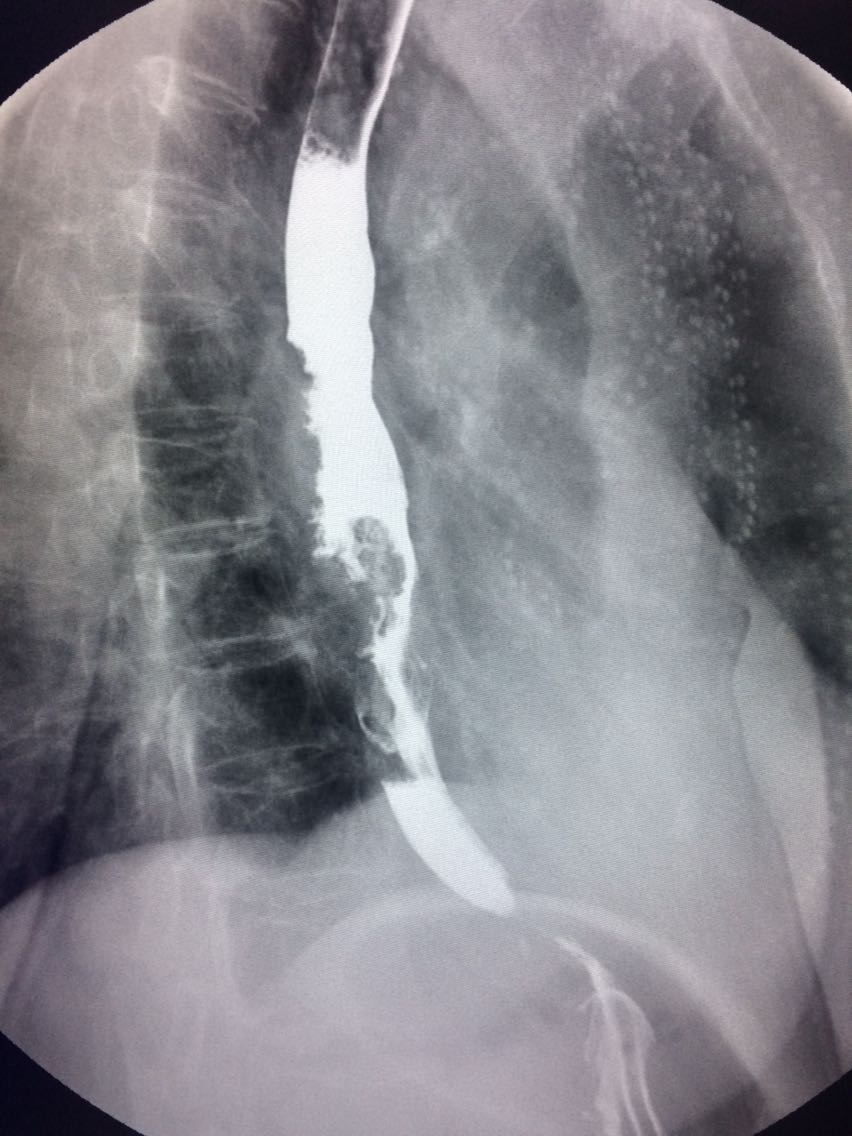

查体未见明显异常。 上消化道造影如图。

诊断食管癌。 造影剂逆流入胆道。